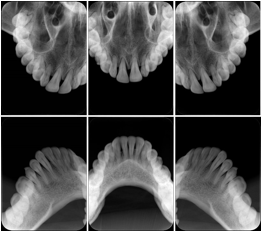

2. A patient requests cosmetic surgery to enhance their facial appearance. The case requires consultation between an orthodontist in New York and an oral surgeon in California. The cephalometric series of 2D projections constructed from a volumetric CT data set that is used for the discussion is arranged by a Structured Display for transfer between the two practitioners.

Cephalometric Series Structured Display

Figure OO-2. Cephalometric Series Structured Display

3. A dental provider wishes to capture a series of DICOM IO images for the patient’s dentition. The tooth morphology, teeth are divided into molars, premolars, canines and incisors, and a number of images for each jaw. The anatomic information was captured utilizing the triplet of schema. This standard code sequence is based on ISO 3950-2010, Dentistry - Designation system for teeth and areas of the oral cavity.

Every IO image should have anatomic information either through the primary or modifier sequence.

In most standard cases, images are oriented in structured layouts. These structured displays are useful to be shared between providers for reference purposes.